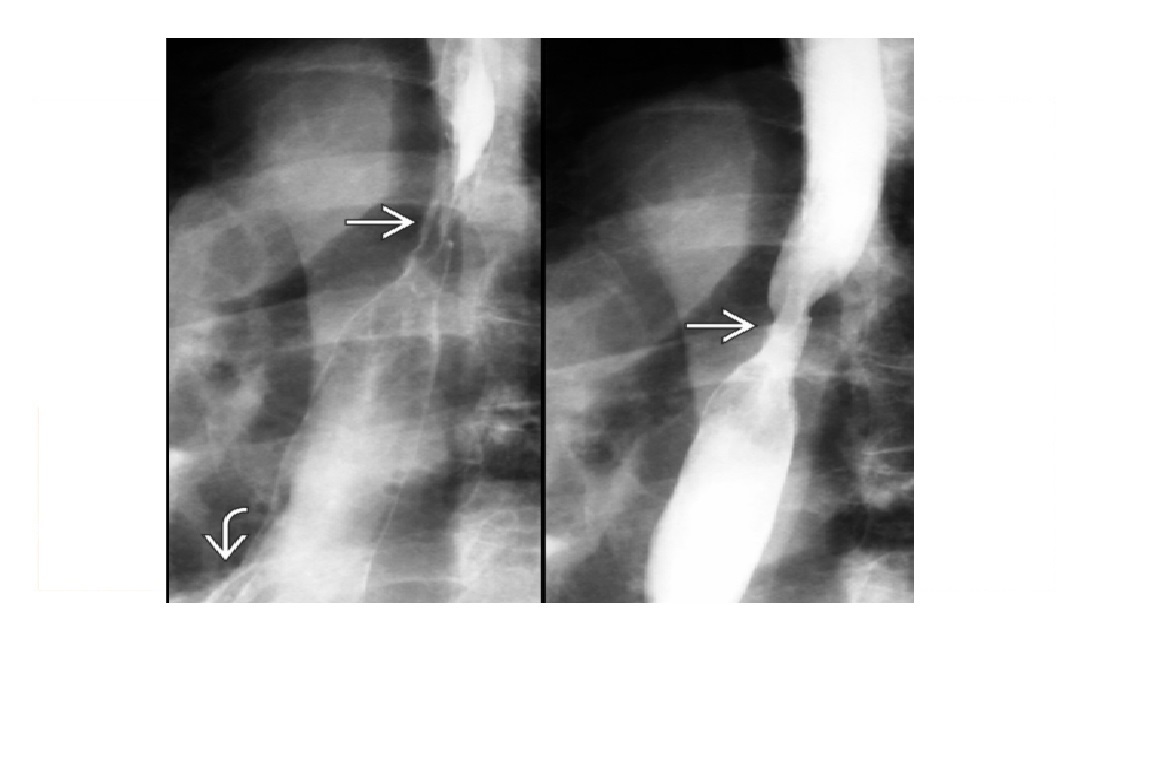

Q

Features of gastric carcinoma?

A

1. Intraluminal mass with no peristalsis through lesion (at fluoroscopy)

- Antral mass causing outlet obstruction

2. Ulcer -

Width > depth, nodular edges

obliteration of surrounding areae gastricae

3. Infiltrative -

Diffuse infiltration of gastric wall; non-peristaltic, non-distensible = **Linitis plastica (leather bottle) ***

**Pseudoachalasia: Fundal carcinoma may destroy myenteric plexus

Oesophageal obstruction, dilated lumen, diminished peristalsis; mistaken for primary achalasia - Pseudo the GE junction doesnt relax

Krukenberg tumor: Metastases to ovaries via peritoneal seeding

Early epigastric nodes

How well did you know this?